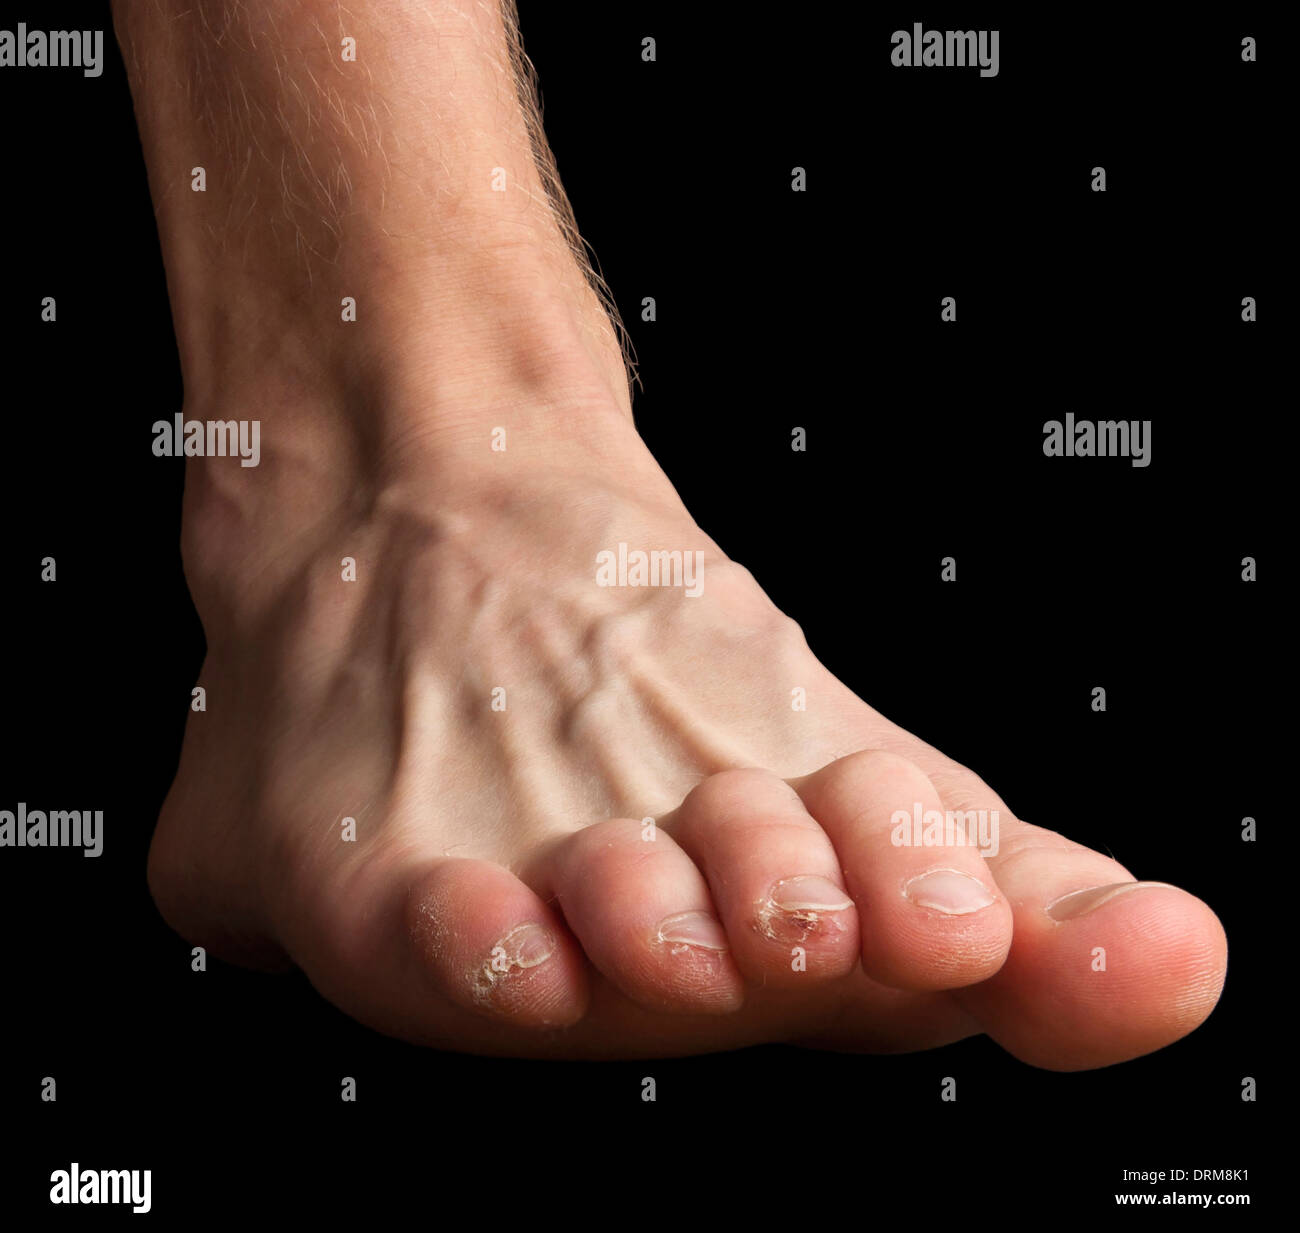

RFDRM8K1–Ein menschlicher Fuß mit den Zehen verletzt. Häutung Haut- und gebrochenen Bläschen und ein Blut-Blister.